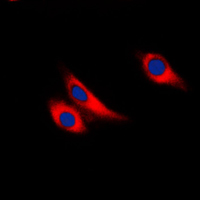

Immunofluorescent analysis of Galectin 9 staining in THP1 cells. Formalin-fixed cells were permeabilized with 0.1% Triton X-100 in TBS for 5-10 minutes and blocked with 3% BSA-PBS for 30 minutes at room temperature. Cells were probed with the primary antibody in 3% BSA-PBS and incubated overnight at 4 °C in a humidified chamber. Cells were washed with PBST and incubated with a DyLight 594-conjugated secondary antibody (red) in PBS at room temperature in the dark. DAPI was used to stain the cell nuclei (blue).